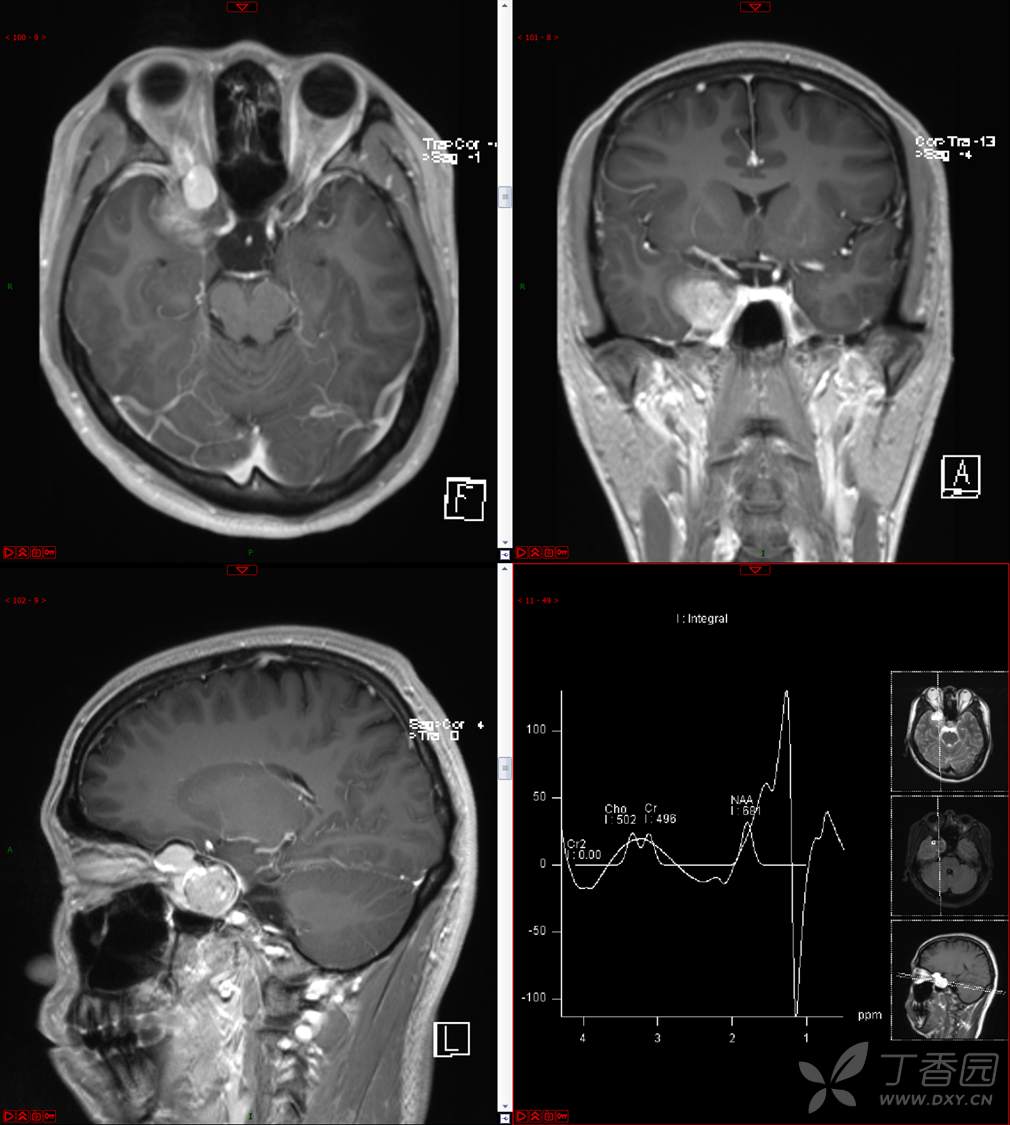

【影诊笔记534】青年男性,视物模糊就诊,CT、MRI、MRS齐全,请分析~~~

主 诉:视物重影5天。

现病史:患者5天前无明显诱因出现视物重影,表现为右视时视物成双,无头痛、头晕,无恶心、呕吐,无面部麻木、饮水呛咳等,于当地医院就诊,行颅脑MR示“颅内占位性病变”,现为求进一步治疗来诊。患者病来精神可,饮食、睡眠正常,体重无明显变化。